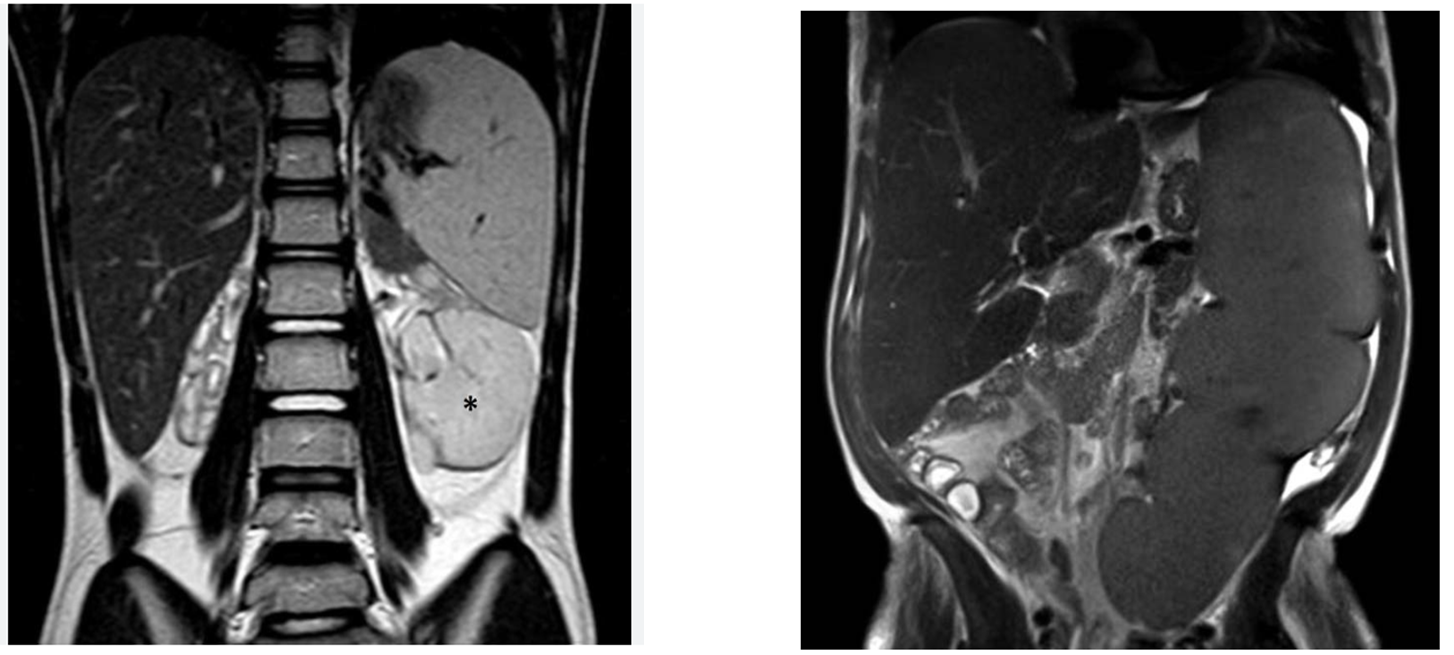

Pancreatic Pseudocyst

is defined as fluid-filled cavity.

They occur due to inflammation, necrosis, or hemorrhage.

Causes:

Acute pancreatitis

Trauma